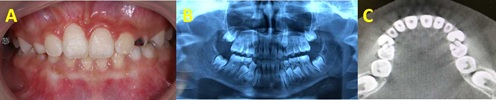

A 8-year-old boy reported to the Department of Orthodontic Dentistry with a complaint of missing upper front tooth. History revealed that the patient had an injury to the front tooth region 4 years ago, due to a fall. Intraoral examination revealed a missing right central incisor without space loss (Figure 1A). CBCT revealed an impacted malformed central incisor which necessitated further investigations (Figure 1B and 1C). To assess the detailed three-dimensional positioning of the root in orthogonal and oblique planes, cone-beam computed tomography was advised, which revealed dilaceration root with more than 90° angulation and crown directed toward the ANS (Figure 1B and 1 C).

Figure 1 (A to C): A) Intraoral photograph. B and C) CBCT showing impacted dilacerated central incisor.